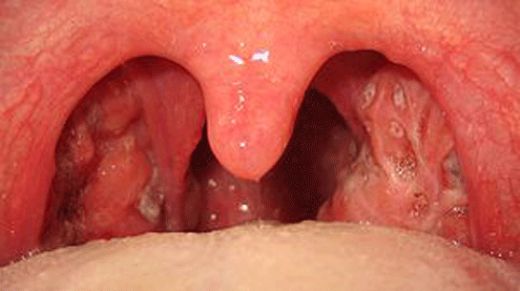

Bademcik İltihabı Nedir?Bademcik iltihabı, genellikle viral veya bakteriyel enfeksiyonlar sonucunda bademciklerin iltihaplanmasıdır. Bademcikler, boğazın arka tarafında bulunan ve vücudu enfeksiyonlara karşı koruyan lenfatik dokulardır. Bu durum, genellikle çocuklarda daha sık görülür, ancak her yaş grubunu etkileyebilir. Bademcik iltihabı, boğaz ağrısı, yutma zorluğu, ateş ve genel bir rahatsızlık hissi ile kendini gösterir. Bademcik İltihabının Belirtileri Bademcik iltihabının belirtileri genellikle şunlardır:

Ek Bilgiler Bademcik iltihabı, bazen diğer sağlık sorunlarına yol açabilir. Örneğin, bademciklerin sürekli iltihaplanması, uyku apnesi gibi sorunlara neden olabilir. Bu nedenle, bademcik iltihabı belirtileri görüldüğünde bir sağlık profesyoneline başvurulması önemlidir. Ayrıca, bademcik iltihabının tedavisi sırasında evde uygulanabilecek doğal yöntemler de mevcuttur, ancak bu yöntemlerin etkili olup olmadığını değerlendirmek için mutlaka bir doktora danışılması önerilmektedir. Bademcik iltihabı, genellikle geçici bir durum olmasına rağmen, tekrarlayan vakalar veya ciddi semptomlar durumunda profesyonel tıbbi yardım alınması gerekmektedir. Tedavi yöntemleri, hastanın genel sağlık durumu, yaş ve belirtilerin şiddetine göre belirlenmektedir. |